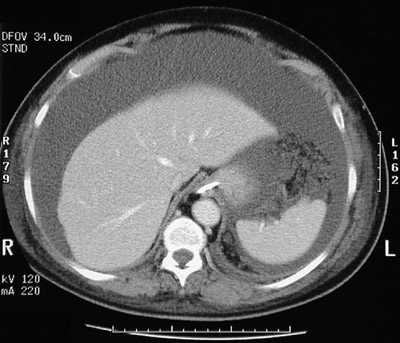

The extensive areas of fluid density in this abdominal CT scan are collections of ascitic fluid in a patient with severe acute necrotizing pancreatitis.